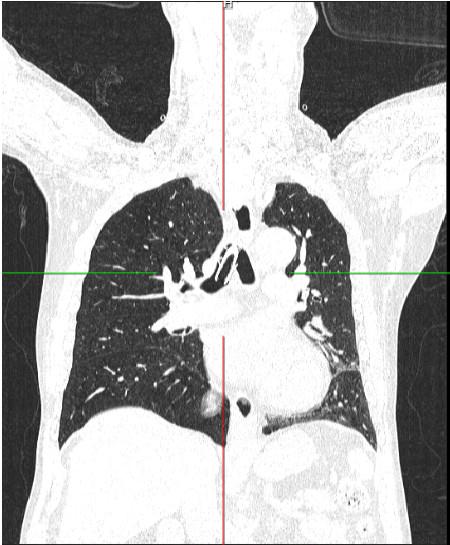

Đó là bệnh nhân Nguyễn Mạnh T (67 tuổi, ở Thanh Hóa). Bệnh nhân có tiền sử hẹp khí quản sau tai nạn giao thông, được mở khí quản vĩnh viễn 11 năm trước, bệnh nhân được hướng dẫn và tự thay nòng của canuyn mở khí quản hàng ngày. Từ khi mở khí quản, bệnh nhân không đi khám và chưa thay canuyn lần nào. Khoảng 14 giờ ngày 17/10/2022, bệnh nhân ho cơn, gãy canuyn mở khí quản và rơi vào trong đường thở, được cấp cứu tại Bệnh viện tỉnh Thanh Hóa. Bệnh nhân còn khó thở nhiều, ho đờm, không sốt, đau tức ngực, sau đó được chuyển Bệnh viện Hữu nghị Việt Đức, chẩn đoán Dị vật khí quản, phế quản gốc (P); tiên lượng khó khăn trong can thiệp lấy dị vật và được chuyển đến Trung tâm Hô hấp – Bệnh viện Bạch Mai trong tình trạng tỉnh, ho lọc xọc đờm, không sốt, khó thở nhẹ, huyết động ổn định. Chụp cắt lớp vi tính ngực có dựng hình khí phế quản cho thấy hình ảnh dị vật dạng ống trong khí quản và phế quản gốc (P), kích thước 5 x 1,5 cm, tắc hoàn toàn khí quản phía trên lỗ mở khí quản.

Hình ảnh chụp cắt lớp vi tính, dị vật đường thở